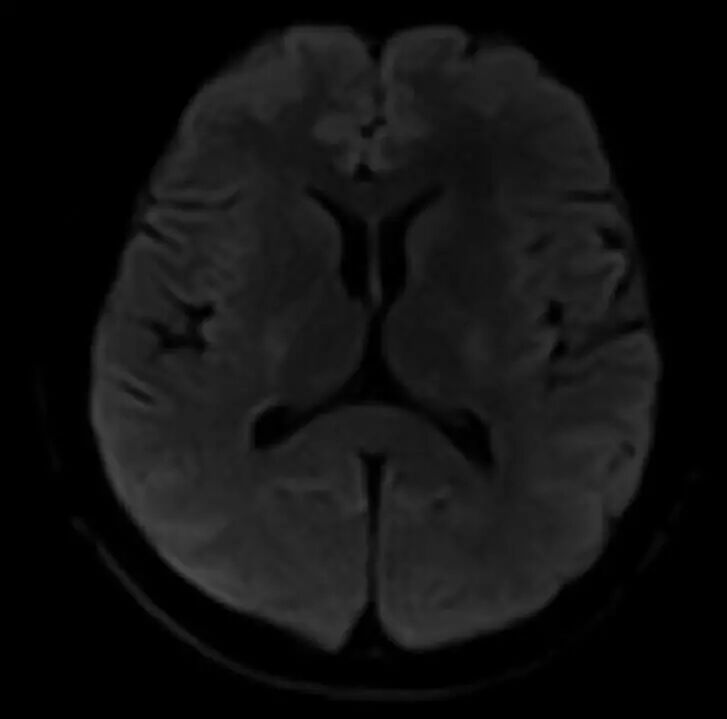

脑部弥散

MRCP